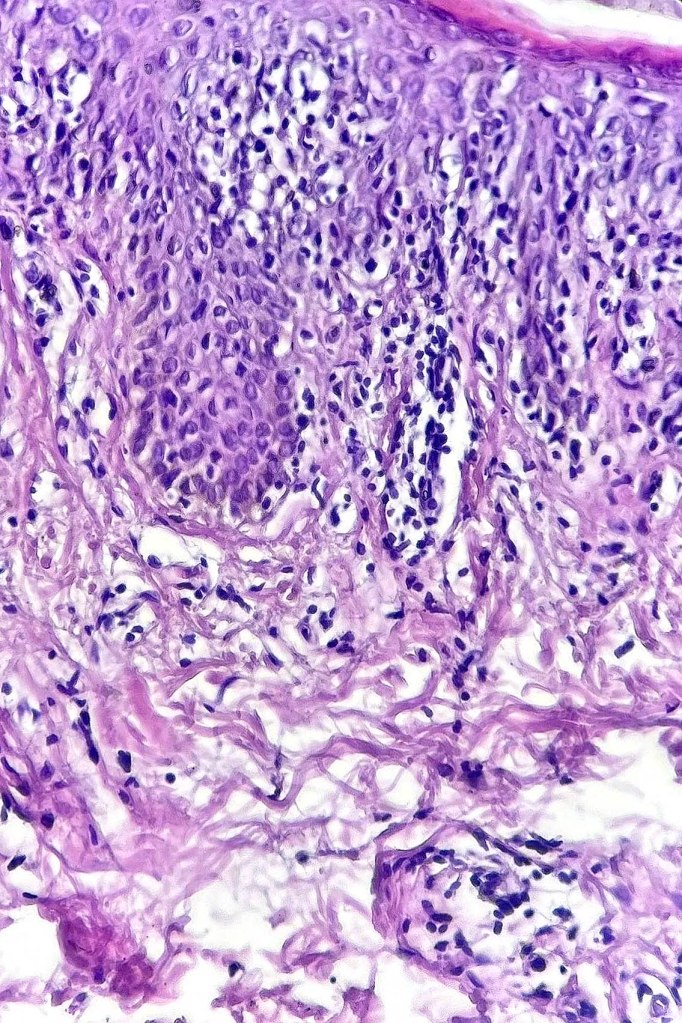

Histological features

•Indistinguishable from classical mycosis fungoides with the additional feature of marked pigmentary incontinence

•CD8+ve cells may predominate

•Hypopigmentation likely associated with melanocytic toxicity & reduced melanocyte population although this isn’t always a feature